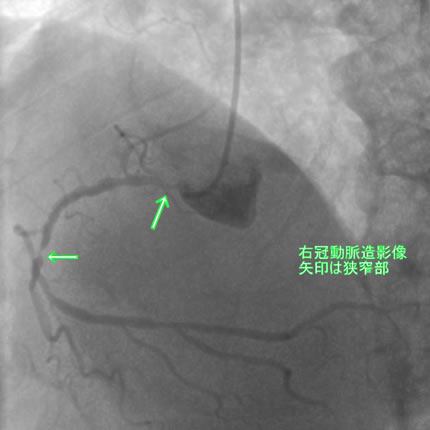

図1-1 右冠動脈造影

よく解らないと思いますが、冠動脈に多数の狭窄があることと冠動脈が「こぶ状変化(医学用語で瘤状変化)」を生じているのが解ると思います。